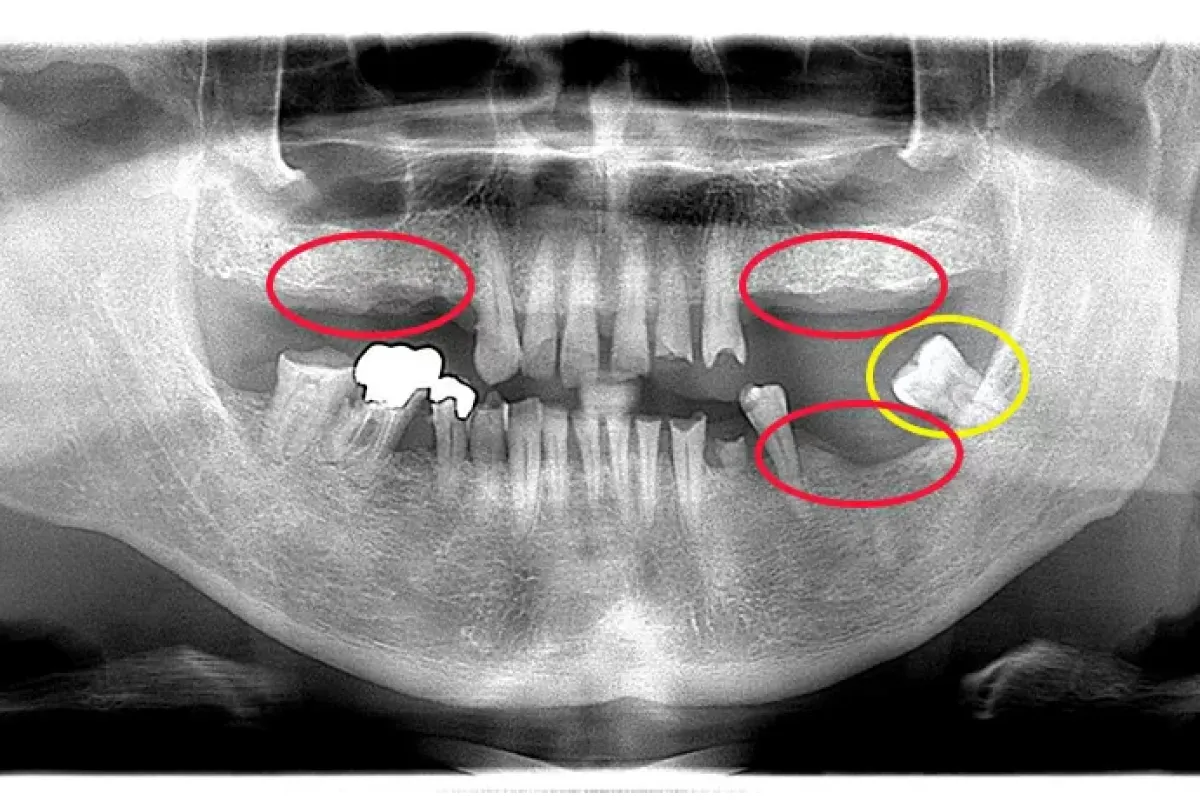

患者様情報 60代女性 患者様のお悩み 被せものがはずれた、前歯のブリッジがぐらぐらする 治療概要 虫歯治療、詰め物・被せ物、インプラント 提案内容 奥歯は金属修復補綴物の劣化、隙間からの虫歯があったので治 […]